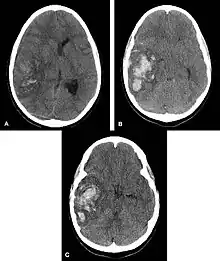

| Intraparenchymal hemorrhage | |

| Multiple intraparenchymal hemorrhage | |

Intraparenchymal hemorrhage (IPH) is one form of intracerebral bleeding in which there is bleeding within brain parenchyma. The other form is intraventricular hemorrhage (IVH).[1]